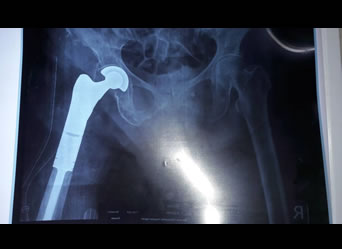

Proximal femoral endoprosthetic replacement | total hip replacement | total knee replacement distal femoral endoprosthetic replacement

Proximal Femoral Endoprosthetic Replacement